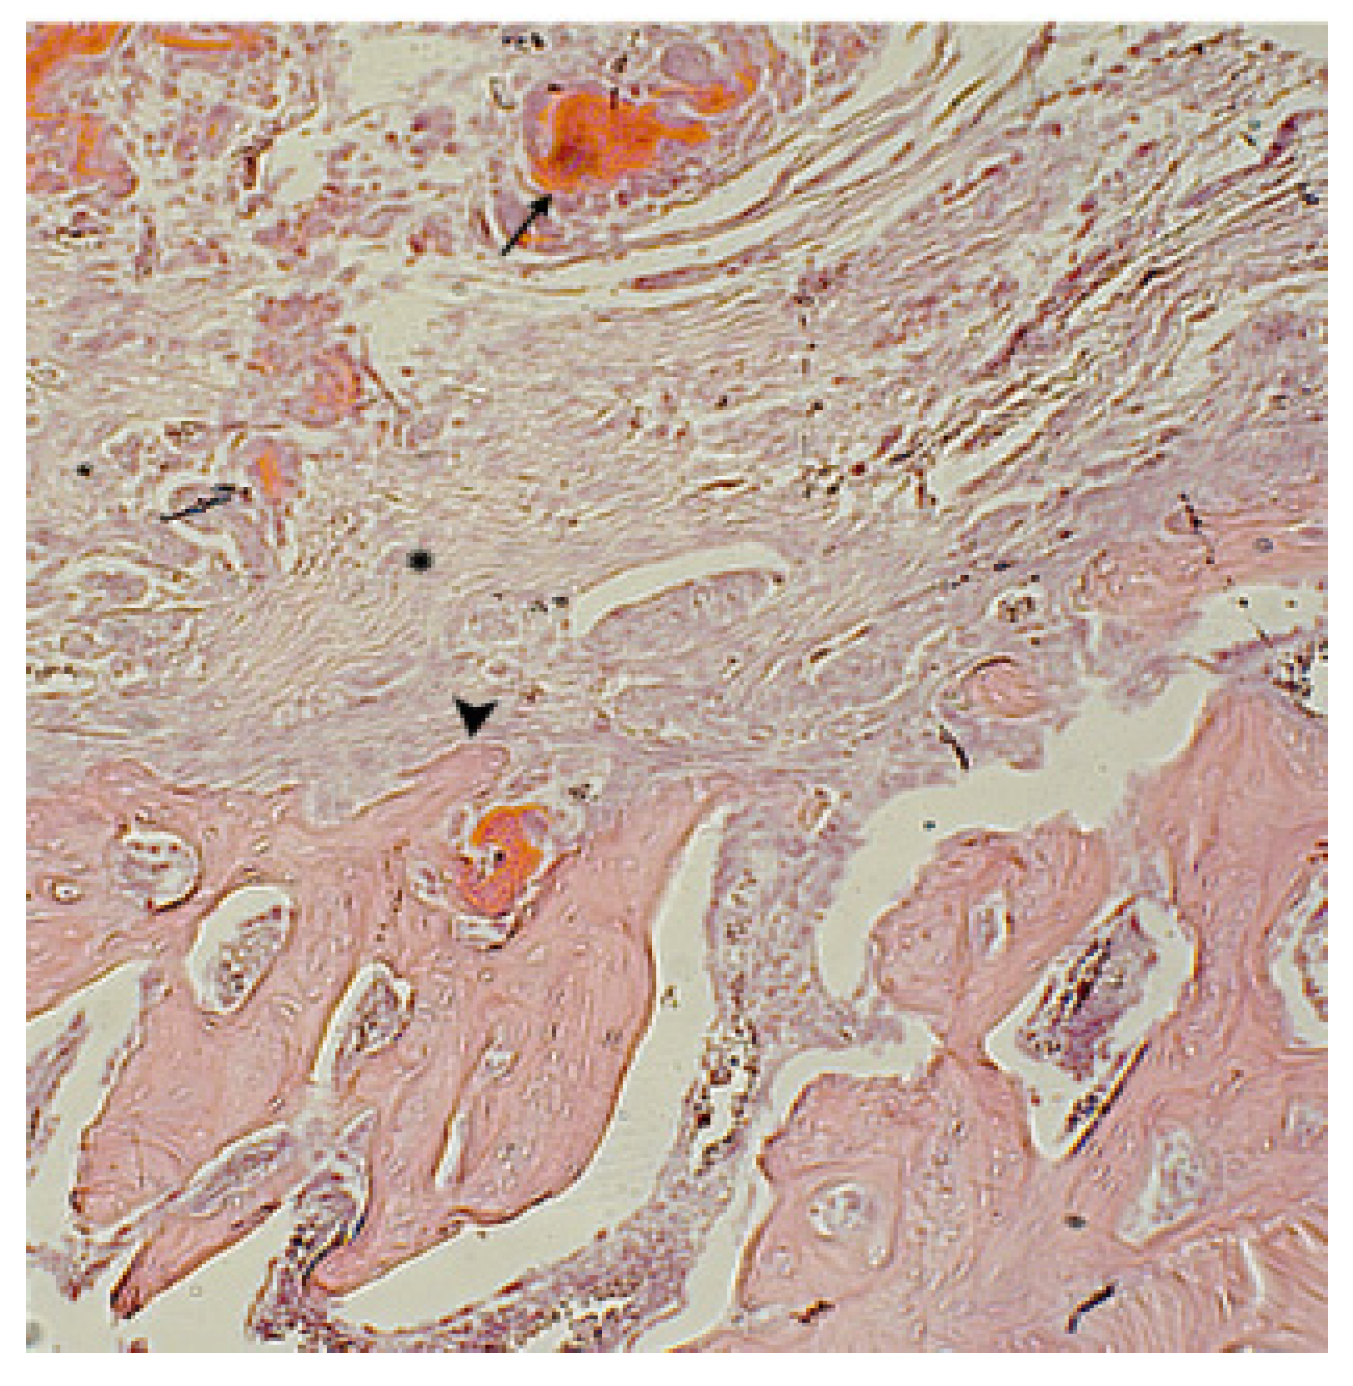

). Hematoxylin-eosin staining. Magnification x400.